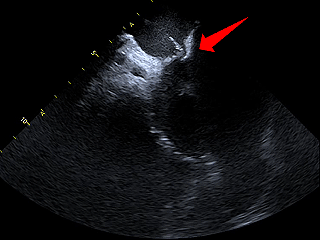

房间隔穿刺

房间隔靠后靠下进行穿刺后造影确认穿刺位点合适